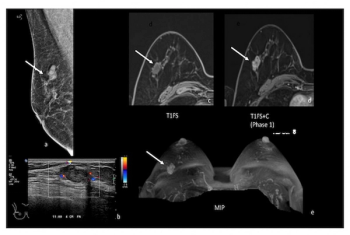

Findings from a new pilot study showed that low-dose positron emission mammography (PEM) detected 96 percent of malignant index lesions and had a 46 percent lower false-positive rate in comparison to breast MRI.